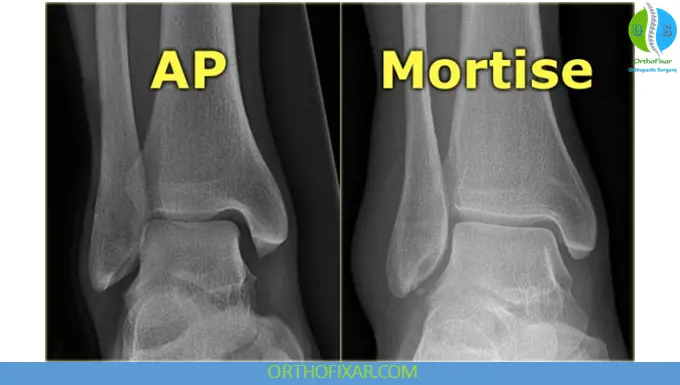

3. Mortise View (Anteroposterior Oblique – Routine Ankle)

The mortise view is obtained by internally rotating the leg approximately 15–20 degrees.

- Provides a clear, unobstructed view of the ankle mortise

- Essential for assessing syndesmotic integrity

- Widely used in trauma cases and fracture classification

This is one of the most important views in routine ankle joint X-ray evaluation.